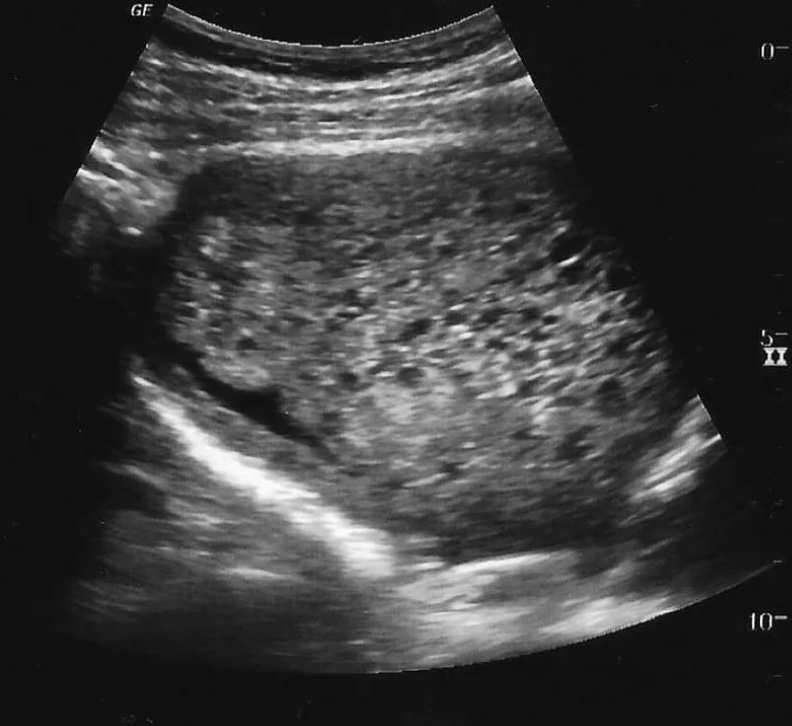

Sonographically you’ll see an enlarged , round uterus with many cystic spaces classically referred to as “bunch of grapes” 🍇.

Case 2